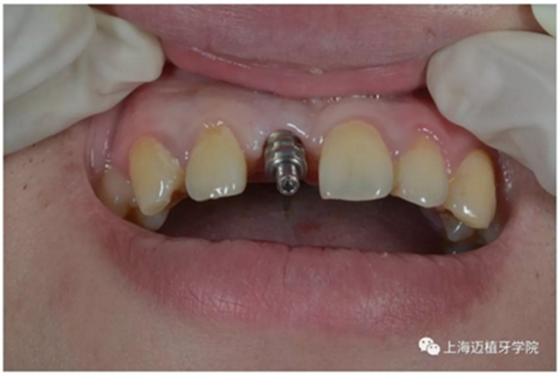

戴牙前口內(nèi)照片:

去除愈合基臺(tái):

口內(nèi)個(gè)性化基臺(tái):